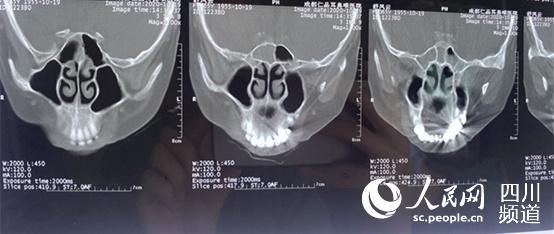

舒紅的鼻竇CT片。徐田莉 攝